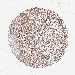

KIDNEY RENAL CLEAR CELL CARCINOMA (VALIDATION) - Interactive survival scatter ploti

The Survival Scatter plot shows the clinical status (i.e. dead or alive) for all individuals in the patient cohort, based on the same data that underlies the corresponding Kaplan-Meier plots. Patients that are alive at last time for follow-up are shown in blue and patients who have died during the study are shown in red.

The x-axis shows the expression levels (FPKM) of the investigated gene in the tumor tissue at the time of diagnosis. The y-axis shows the follow-up time after diagnosis (years). Both axes are complimented with kernel density curves demonstrating the data density over the axes. The top density plot shows the expression levels (FPKM) distribution among dead (red) and alive patients (blue). The right density plot shows the data density of the survived years of dead patients with high and low expression levels respectively, stratified using the cutoff indicated by the vertical dashed line through the Survival Scatter plot. This cutoff is automatically defined based on the FPKM cutoff that minimizes the p-score. The cutoff can be changed by dragging the vertical line or by entering a cutoff value in the square labeled "Current cut-off".

Under the Survival Scatter plot the p-score landscape (black curve; left axis) is shown together with dead median separation (red curve; right axis). Dead median separation is the difference in median mRNA expression between patients who have died with high and low expression, respectively. It is calculated as follows: median FPKM expression of dead patients with high expression - median FPKM expression of dead patients with low expression. This is intended to aid the user in visually exploring custom cutoffs and the associated p-scores and dead median separation.

Individual patient data is displayed and can be filtered by clicking on one or more of the category buttons on the top of the page. Categories describing expression level and patient information include: high, low, alive, dead, female, male and tumor stages. The scale of the x-axis can be toggled between linear and log-scale by clicking on the "x log" button. Mouse-over function shows TCGA ID, patient information and mRNA expression (FPKM) for each patient.

& Survival analysisi

Kaplan-Meier plots summarize results from analysis of correlation between mRNA expression level and patient survival. Patients were divided based on level of expression into one of the two groups "low" (under cut off) or "high" (over cut off). X-axis shows time for survival (years) and y-axis shows the probability of survival, where 1.0 corresponds to 100 percent.

EEF2 is not prognostic in Kidney Renal Clear Cell Carcinoma (validation)

Best expression cut offi

Based on the FPKM value of each gene, patients were classified into two groups and association between prognosis (survival) and gene expression (FPKM) was examined. The best expression cut-off refers the FPKM value that yields maximal difference with regard to survival between the two groups at the lowest log-rank P-value. Best expression cut-off was selected based on survival analysis .

When clicking on this number, the vertical dashed line indicating cut-off, the interactive survival plot, and the Kaplan-Meier curve will be adjusted to show results based on the best expression cut-off.

: 914.34

TCGA RNA samplesi

RNA-seq data is reported as average FPKM (number Fragments Per Kilobase of exon per Million reads), generated by the The Cancer Genome Atlas (TCGA) .

Normal distribution across the dataset is visualized with box plots, shown as median and 25th and 75th percentiles. Points are displayed as outliers if they are above or below 1.5 times the interquartile range. FPKM values of the individual samples are presented next to the box plot.

Average pTPM 1279.4

Number of samples 100